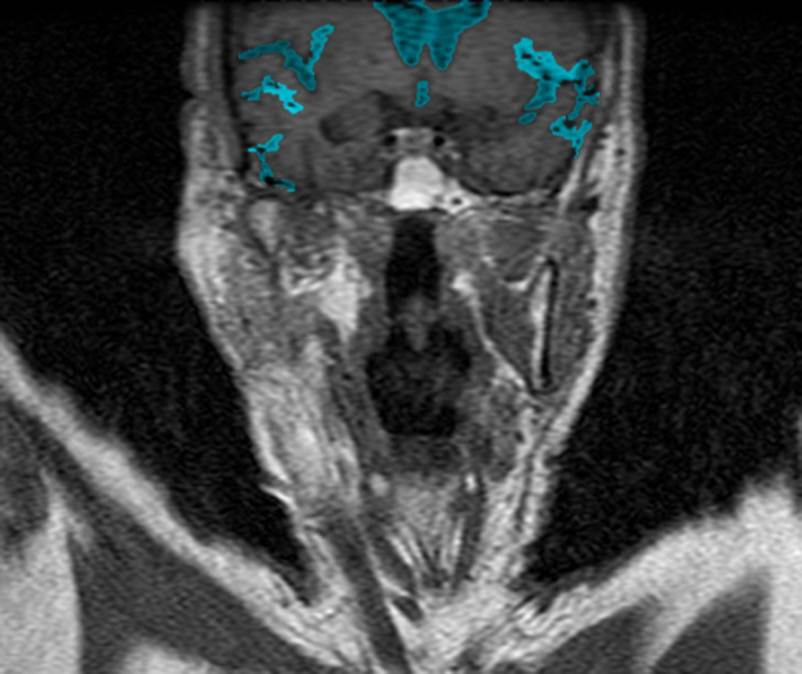

CT: Brain Atrophy